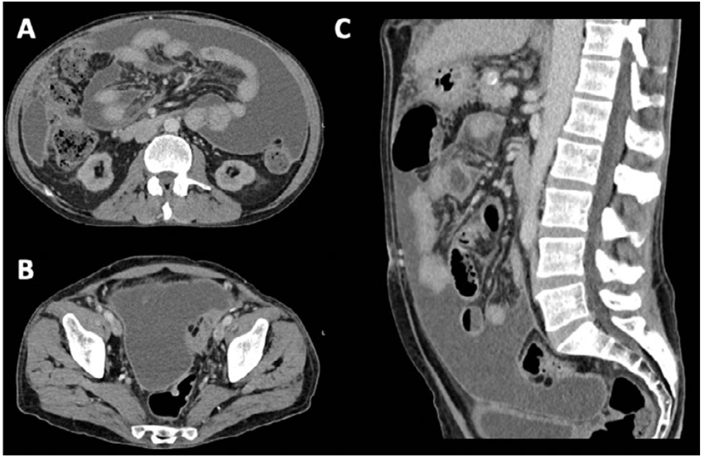

We present a 56‑year‑old man with a relevant past medical history of diabetes with both microvascular‑ and macrovascular end‑organ damage (retinopathy, end‑stage CKD undergoing hemodialysis, and peripheral arterial dis- ease), hypertension, alcoholic liver disease with clinically significant portal hypertension, and dilated cardiomyopathy, which all translated an age‑adjusted Charlson Comorbidity Index of 11 points. Upon presentation to the emergency department, the patient reported a three‑week history of diffuse abdominal pain, accompanied by asthenia, anorexia, and an unintentional weight loss of 1.5 kg. There was no known history of immunosuppression or apparent epidemiological context. Physical examination revealed an emaciated and malnourished male (body mass index [BMI] 15.4 kg/m²) with notable ascites, peripheral edema, and abdominal guarding. Initial laboratory analysis demonstrated expectedly low nutritional parameters (serum albumin 18 g/L, potassium 4.0 mmol/L, pre‑dialysis urea 80 mg/dL) and elevated inflammatory markers (C‑reactive protein [CRP] 172.5 mg/L) without leukocytosis. A thoracoabdominal computed tomography (CT) scan reported bulky and loculated ascites, peritoneum thickening, and diffuse micronodularity of the great omentum and mesentery, favoring peritoneal carcinomatosis (Fig. 1). The patient was admitted for etiologic investigation and continuation of care.

Figure1. CT‑scan transversal (A and B) and sagittal planes (C). Bulky ascites, peritoneum thickening, and diffuse micronodularity of the great omentum and across the mesentery, favoring peritoneal carcinomatosis.